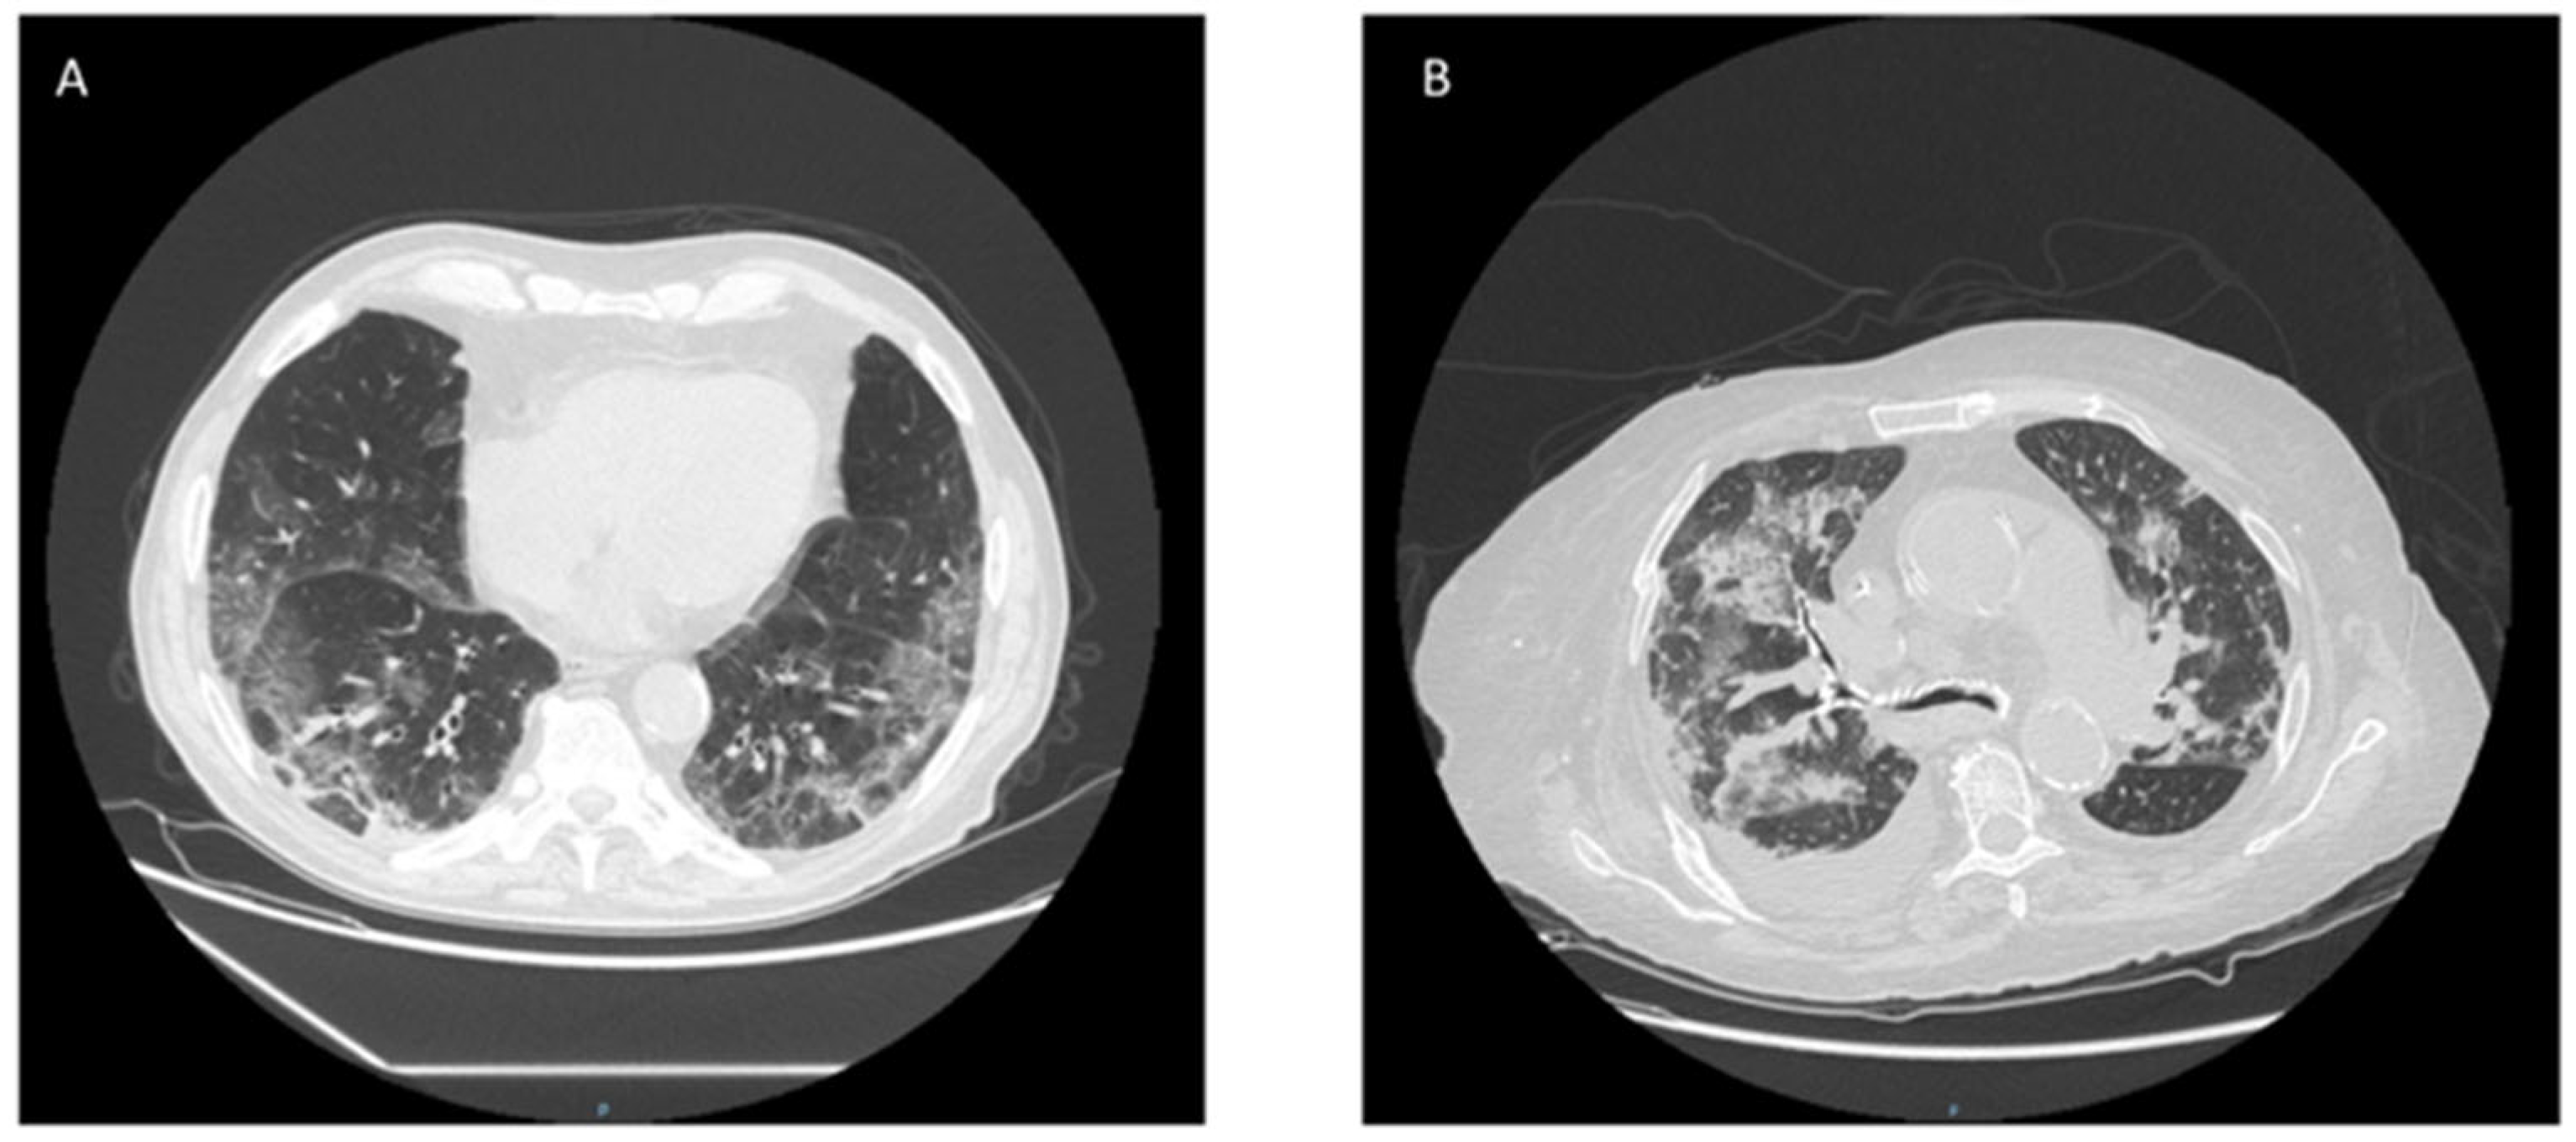

| Admission HRCT | ||||

| Bilateral ground-glass opacity, n (%) | 21(81) | 12 (80) | 9 (60) | 0.176 |

| Unilateral ground-glass opacity, n (%) | 5 (19) | 3 (20) | 2 (40) | 0.234 |

| Bilateral ground-glass opacity, n (%) | 21 (80.8%) | 15 (83.3%) | 8 (100%) | 0.152 |

| Unilateral ground-glass opacity, n (%) | 5 (19.2%) | 3 (16.7%) | 0 | n.a. |